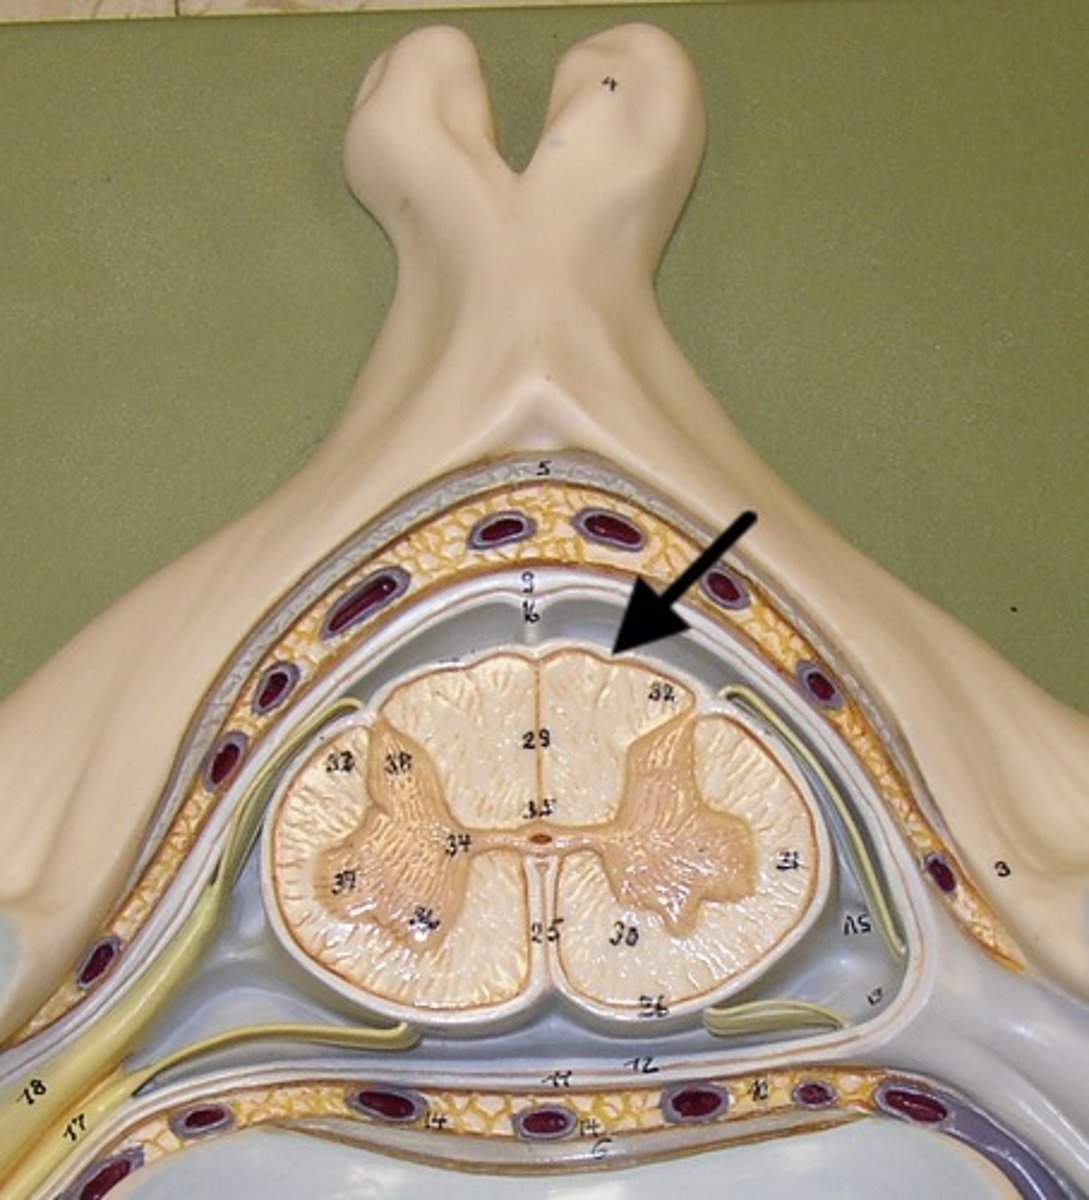

spinal cord structure

white matter of spinal cord

gray matter of spinal cord

posterior gray horn

lateral gray horn

anterior gray horn

posterior white column

lateral white column

anterior white column

central canal of spinal cord

posterior median sulcus

anterior median fissure